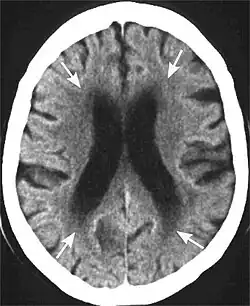

Leukoaraiosis is a particular abnormal change in appearance of white matter near the lateral ventricles. It is often seen in aged individuals, but sometimes in young adults.[1][2] On MRI, leukoaraiosis changes appear as white matter hyperintensities (WMHs) in T2 FLAIR images.[3][4] On CT scans, leukoaraiosis appears as hypodense periventricular white-matter lesions.[5]

The term "leukoaraiosis" was coined in 1986[6][7] by Hachinski, Potter, and Merskey as a descriptive term for rarefaction ("araiosis") of the white matter, showing up as decreased density on CT and increased signal intensity on T2/FLAIR sequences (white matter hyperintensities) performed as part of MRI brain scans.